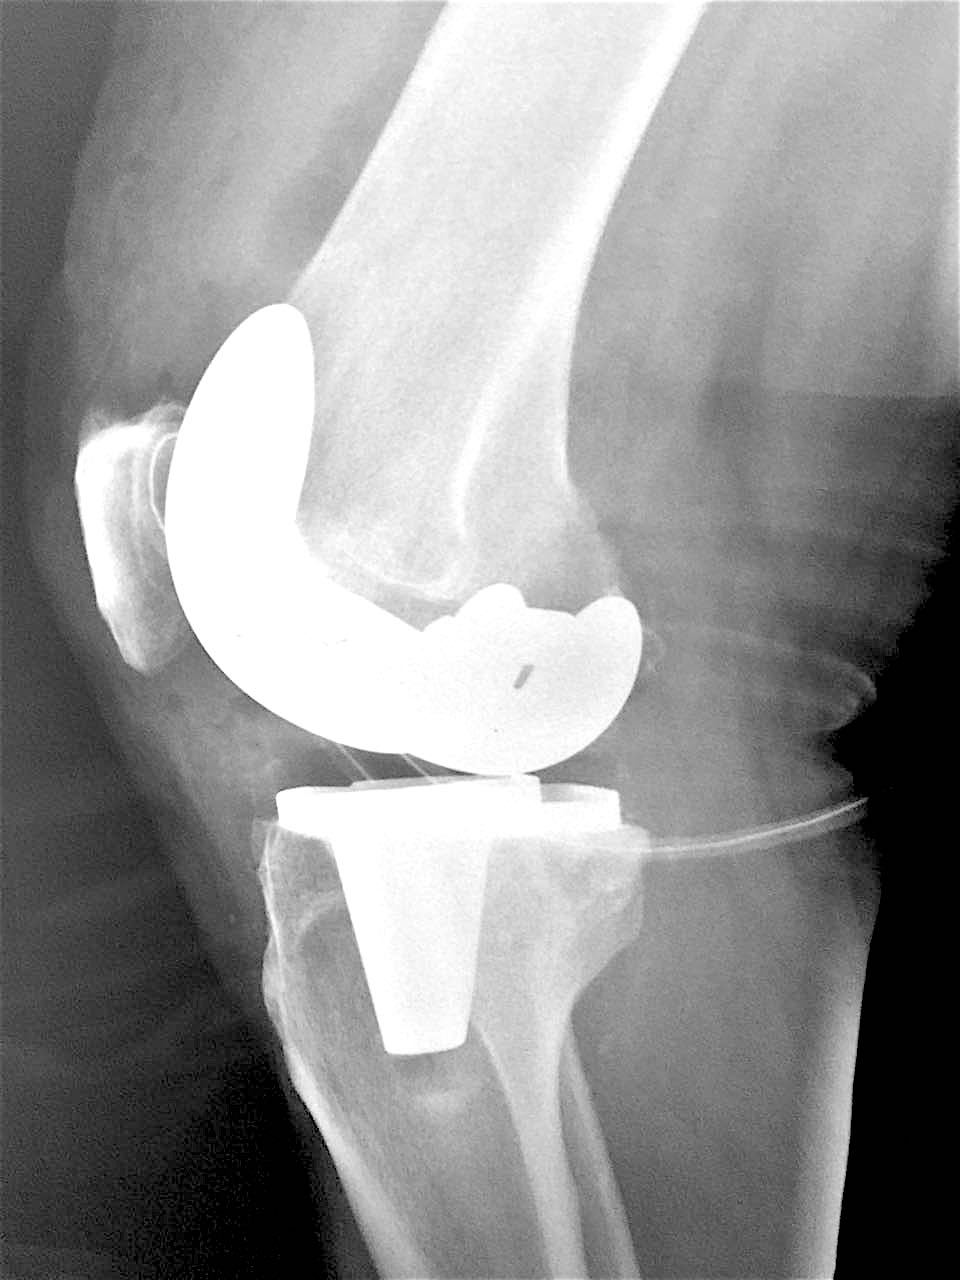

Больной З. 72 года. Диагноз: посттравматический деформириующий правосторонний гонартроз, genu valgum.

Сделано тотальное эндопротезирование коленного сустава, костная аллопластика материалом «Лиопласт».